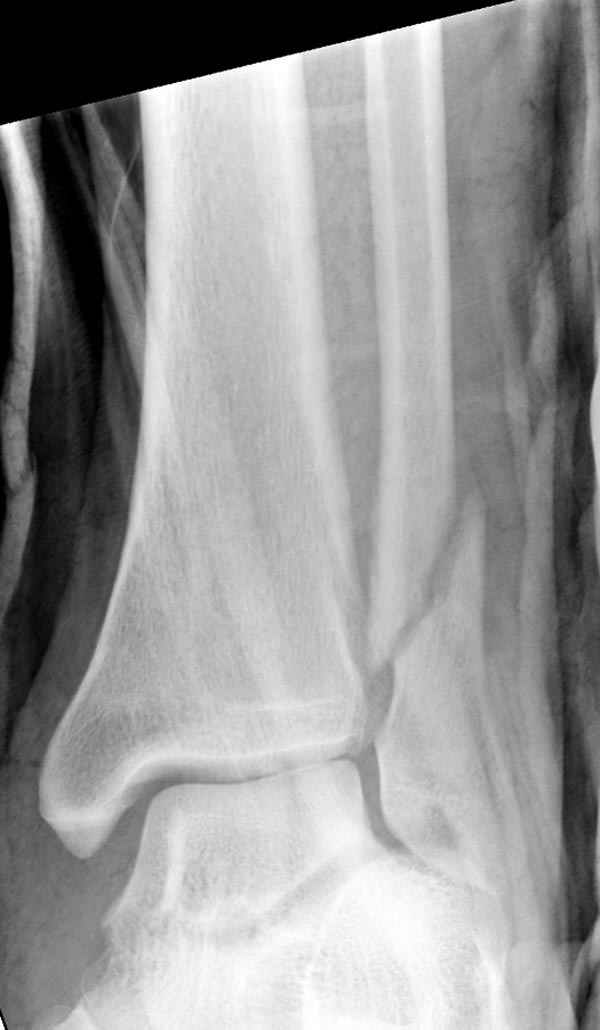

Тему неоднократно разбирали (см. архив), как всегда, недостаточны ренгенологические исследования - кроме прямого и боковых снимков, еще нужна косая ренгенограмма для определения ankle mortise, без мортиз снимка трудно определить высоту и ротацию малоберцовой. (снимки)

Ренгенология даст ответ как классифицировать перелом, на сегодня применяется классификация “Lauge Hansen fracture classification SER supination-external rotation или supination-eversion classification Danis

Weber А, В, С.”

Показания для фиксации: укорочения и ротация малоберцовой, особенно обращают внимание на любой подвывих таранной кости: неустраненый подвывих впоследствии приводит к раннему артрозу. Задний край фиксирует тогда, когда перелом составляет около 25% суставной поверхности голеностопного сочленения и смещение более 2мм.

По снимку ваш случай относится к Weber В, фиксацию производят восстановлением длины малоберцовой кости, под ренгеном (ЭП)контролем, для этого я предпочел бы латеральный доступ, остеотомия по линии перелома, удлинение малоберцовой засчет скоса линии остеотомии, компрессия “lag technique”по линии остеотомии и фиксацию провести латеральной пластиной. Отдельный задний доступ, остеотомия по линии перелома, репозиция и фиксация заднего края вашим предпочтительным методом: 3.5мм шурупом с шайбой или пластиной Antiglide Butress

method. При восстановленном суставе, уменьшится медиальная щель, а при Weber В повреждается только передне-нижняя межберцовая связка синдесмоза, повреждение которой приводит к наружной ротации

малоберцовой, но после восстановления всех смещений, связка автоматический приближается к исходному и нет необходимости восстановления синдесмоза.